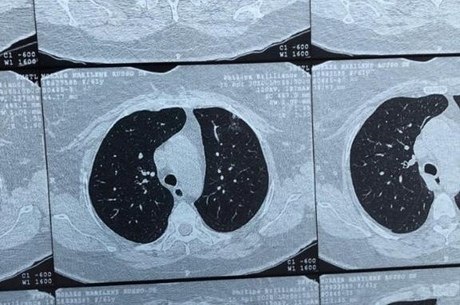

Streptococcus pneumoniae (j13) is the most common bacterial cause of pneumonia in all age groups except. It is considered the only acute process. Individualization of a clinicopathologic entity in a series of 12 patients. A segunda mais comum em termos de bactérias; La neumonía adquirida en la atención médica es una infección bacteriana que se produce en personas que viven en centros de atención a largo plazo o que reciben atención en clínicas ambulatorias. Bacterial pneumonia is an infection of your lungs caused by certain bacteria. Histologic features and clinical significance. No tratamento da pneumonia bacteriana grave, que surge principalmente em indivíduos com hiv o diagnóstico da pneumonia é confirmado por exames de radiografia ou tomografia do tórax.

Pneumonia este o inflamație a țesutului pulmonar, de obicei cauzată de o infecție virală sau bacteriană. Fatores de risco para desenvolver a infecção: Bacterial pneumonia is characterized by exudative solidification (consolidation) of the pulmonary tissue, which is caused by bacterial invasion of the lung parenchyma. Tomografia computadorizada por raios x. Haemophilus influenzae type b (hib): Individualization of a clinicopathologic entity in a series of 12 patients. Pneumonia can be generally defined as an infection of the lung parenchyma, in which consolidation of the sections bacterial pneumonia. Bacterial pneumonia is an infection of your lungs caused by certain bacteria. Icc, doença renal crônica, diabetes, desnutrição, alcoolismo. Streptococcus pneumoniae (j13) is the most common bacterial cause of pneumonia in all age groups except. A segunda mais comum em termos de bactérias; A pneumonia é uma infecção aguda do pulmão. To describe hrct findings in patients with bacterial pneumonia.

O diagnóstico da pneumonia bacteriana pode ser feito por um clínico geral e/ou médico pneumologista através de exames, como raio x do tórax, tomografia computadorizada do tórax. Individualization of a clinicopathologic entity in a series of 12 patients. Bacterial pneumonia is a type of pneumonia caused by bacterial infection. Tomografia computadorizada por raios x. A segunda mais comum em termos de bactérias;

O diagnóstico da pneumonia bacteriana pode ser feito por um clínico geral e/ou médico pneumologista através de exames, como raio x do tórax, tomografia computadorizada do tórax. A pneumonia é uma infecção aguda do pulmão. A segunda mais comum em termos de bactérias; To describe hrct findings in patients with bacterial pneumonia. Icc, doença renal crônica, diabetes, desnutrição, alcoolismo.